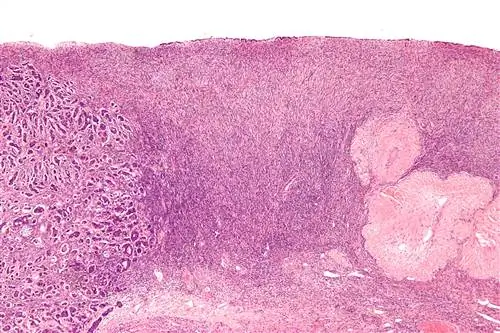

Микрофотография метастатической опухоли [слева] в яичнике при малом увеличении. Эта опухоль метастазировала из опухоли в груди женщины. Фото предоставлено: Wikimedia Commons